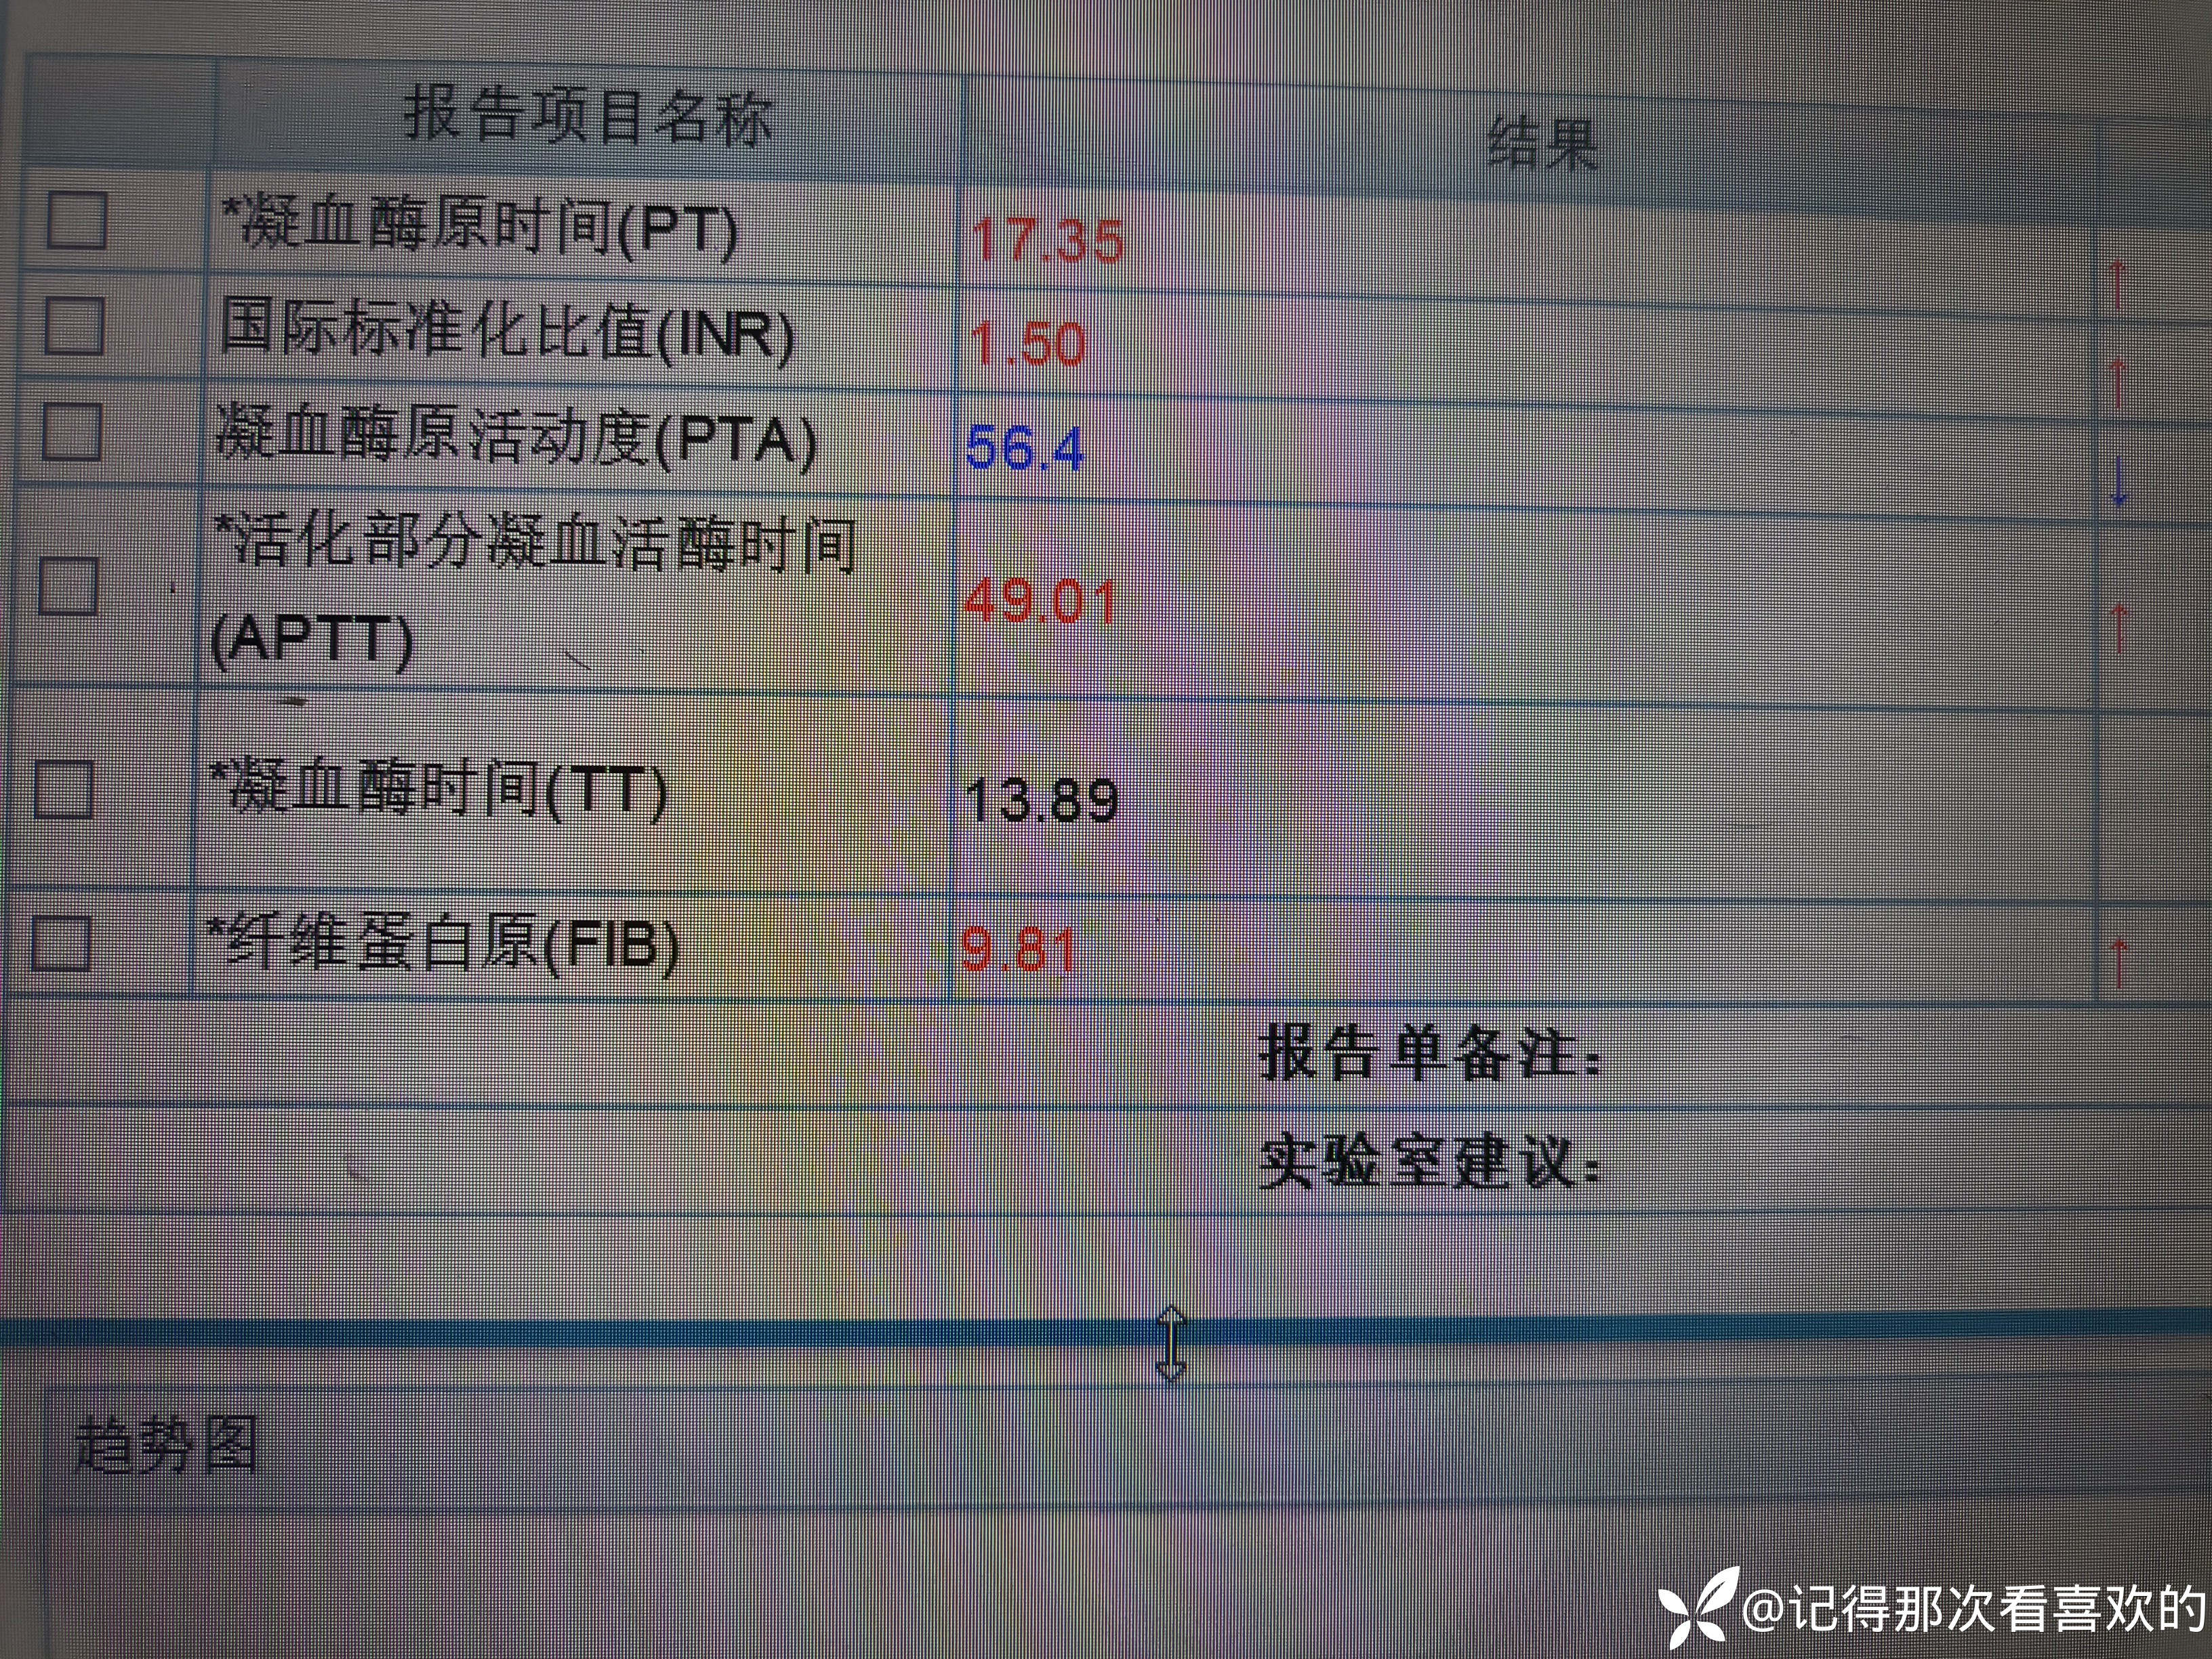

病例特点:患者钟某 男,14岁,以"髋、膝、足肿痛1年余,加重3日。"为主诉入院。现病史:缘于1年前无明显诱因出现左侧髋关节、双足跟、左踝关节、右足第一足趾关节肿胀、疼痛, 疼痛呈持续性,多于阴雨天、活动后症状加重,疼痛未向他处放射、转移,症状严重时行走困难。遂就诊于我科,查"HLA-B27(+)、CRP 70mg/L、骶髂MR:骶髂关节肿胀",诊断为"强直性脊柱炎",先后予皮下注射"司库其尤单抗150mg qw、阿达木单抗40mg q2w",上述症状较前好转,此后不规律用药,于半年前自行停用上述药物,未再规律随诊。3日前再发左膝、双肘关节肿痛,性质同前,程度较前加重,影响行走,伴有发热,体温最高达39℃,自行服用退烧药(具体不详)后体温较前下降,上述关节肿痛无明显改善。现为求进一步治疗,就诊我院,门诊拟"强直性脊柱炎"收住入院。体格检查:T36.6℃ P138次/分 R50次/分BP/120/68mmHg 专科情况:生命征平稳,神志清楚,双肺呼吸音清,未闻及干湿啰音,心律齐,各瓣膜听诊区未闻及杂音,全腹软,无压痛及反跳痛,未触及包块,双肘、左膝关节肿胀、压痛、触之皮温高。双下肢无浮肿,病理征未引出。

诊疗计划:1.入院予二级护理,监测血压、脉搏、呼吸。2.入院完善三大常规、凝血、生化、骶髂MR、彩超、CT、心电图等相关检查评估病情。3.治疗上暂予抗炎镇痛,辅以护胃治疗,待相关检查结果回报后进一步治疗,本次就诊拟行生物制剂治疗,予完善骨保护药物,传染病相关检查排除禁忌症,患者本次发病伴有发热达39℃,追问病史患者诉偶有干咳不适,目前已改善,予完善呼吸道病原学检查明确病情。4.患者Padua评分1分,属于发生VTE低危风险,实行VTE基本预防,动态评估Padua评分。5.已将目前病情及现有临床诊断以及存在疾病复杂性、个体的差异性、对治疗的反应不同、鉴于目前医学技术水平有限,和下一步相关诊疗详细充分告知患者家属,取得家属的理解并同意配合下一步诊疗及检查。6.NRS-2002评分3分,目前患者营养状态尚可,进食情况尚可,根据病情变化动态评估。